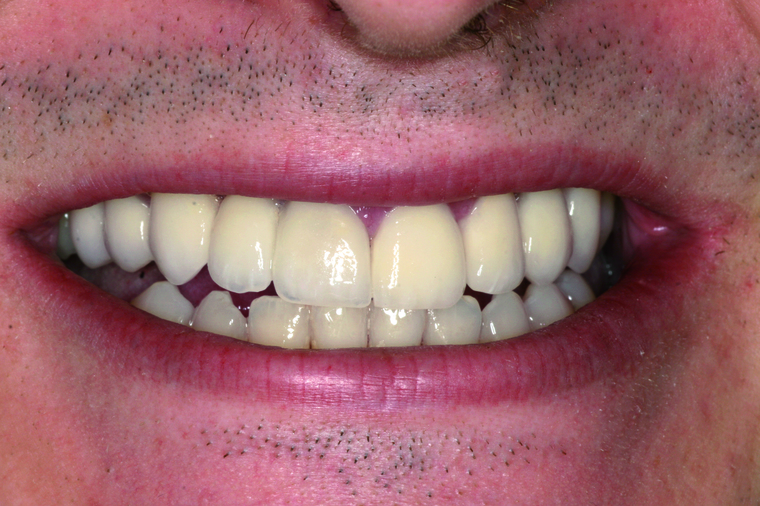

Viele Kunden die zu uns nach Salzburg kommen benötigen eine Generalsanierung der Zähne. Gründe dafür sind Zahnarztangst, Zeitmangel und schlechte Erfahrungen in der Kindheit. Unser Konzept ist genau auf diese umfangreichen Fälle abgestimmt:

Bei einer Generalsanierung müssen alle zahnmedizinischen Bereich in Betracht gezogen werden, dies beginnt bei der Aufklärung und Prophylaxe, gefolgt von Zahnfleischbehandlungen und Kariestherapie, eventuellen Zahnentfernungen, Knochenaufbauten und wird durch ästhetischen Zahnersatz abgeschlossen. Unser Recall-System hält die erreichte Zahnsanierung über lange Jahre stabil.